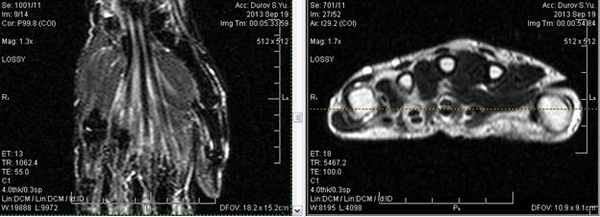

(Слева) МР-артрография в режиме Т1ВИ FS, коронарный срез: определяется разрыв тыльной части ЛПС. Контрастный препарат через дефект распространяется в среднезапястный сустав. Также отмечается разрыв треугольного фиброзно-хрящевого комплекса (ТФХК), вследствие ко торого контрастный препарат поступает в дистальный лучелоктевой сустав.

(Справа) МР-артрография в режиме Т1ВИ FS, коронарный срез, этот же пациент: определяются разрывы мембранозной части ЛПС и мембранозной части треугольного фиброзно-хрящевого диска. (Слева) МР-артрография в режиме Т1ВИ FS, аксиальный срез: визуализируется интактный тыльный пучок, ладонный пучок поврежден. Следует отметить расширение суставной щели, истончение хряща и кисто-зоподобную перестройку.

(Справа) МР-артрография в режиме Т1ВИ FS, коронарный срез: определяется консолидированный перелом дистального отдела лучевой кости. Конгруэнтность суставных поверхностей нарушена. В ладьевидно-полулунном промежутке видна рубцовая ткань. Отмечается распространение контраста в среднезапястный сустав, что, вероятно, обусловлено рубцеванием или сбросом контрастного препарата из лучезапястного сустава в дистальный лучелоктевой сустав через дефекте ТФХК. (Слева) Артрография, заднепередняя проекция, кисть отклонена в локтевую сторону: визуализируется увеличение ладьевидно-полулунного промежутка, однако контрастный препарат в среднезапястный сустав не поступает.

(Справа) МР-артрография в режиме Т1ВИ FS, коронарный срез, этот же пациент: отмечается, что ладьевидно-полулунная связка интактна. Выявленные изменения свидетельствуют о ее заживлении после разрыва.